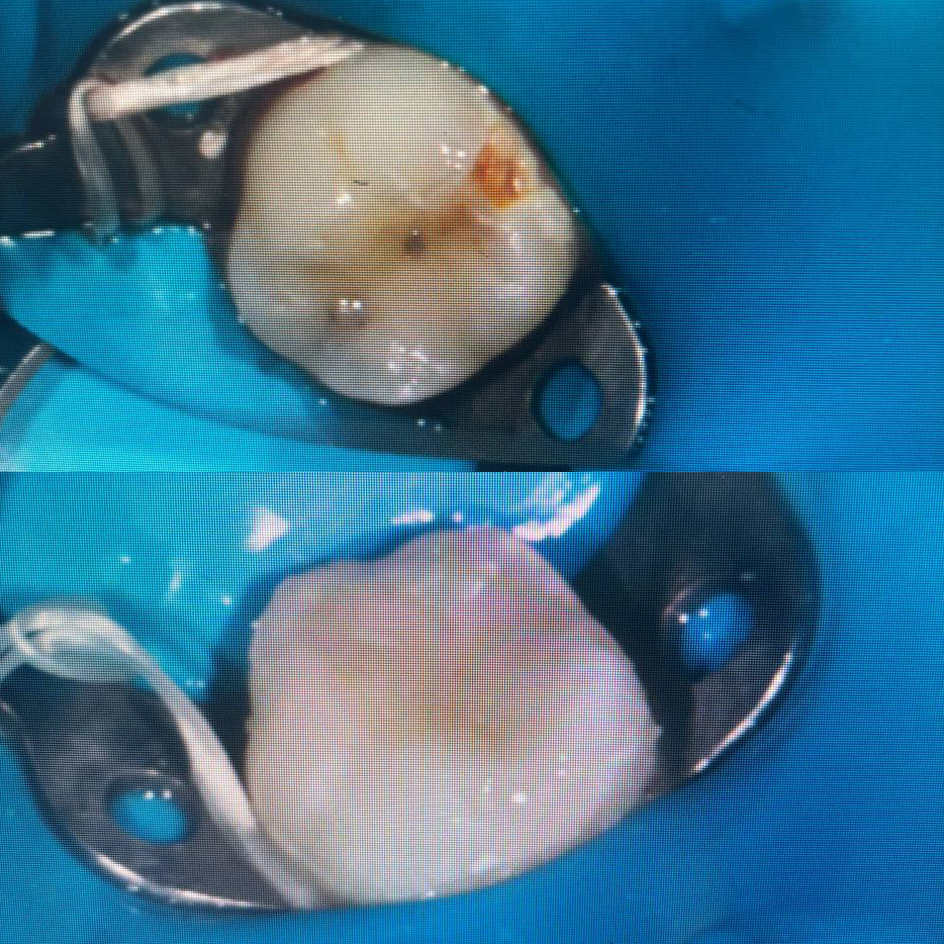

Лечение кариеса

до/после